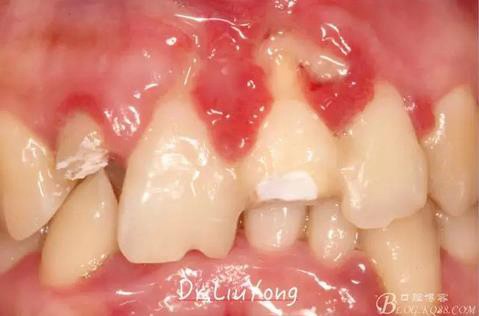

檢查:面部對(duì)稱無(wú)腫脹畸形,張口度正常,口內(nèi)檢查可見(jiàn)A2牙冠缺失,可見(jiàn)直徑約1.5mm左右穿髓孔,冷熱刺激痛+,叩痛+,探痛+,近中斷面探診位于齦下1.5mm,A1B1B2松動(dòng)2-3度,B1牙冠缺失1/2,冷熱刺激痛-,叩痛+,B2牙冠完整,A2-B2牙齦紅腫,探診極易出血,全口口腔衛(wèi)生差,牙結(jié)石++,A1B1之間牙齦乳頭紅腫嚴(yán)重,B1唇側(cè)牙齦萎縮明顯,牙齦邊緣可見(jiàn)縫線兩處,局部有滲出,齦緣冠方1mm處見(jiàn)白色骨塊,松動(dòng),觸痛明顯,觸及骨塊時(shí)可見(jiàn)B1及B2近中唇側(cè)牙齦動(dòng)度,B1B2之間唇側(cè)牙齦乳頭缺失,B2近中根面可見(jiàn)大量牙結(jié)石。重度深覆合,牙尖交錯(cuò)位時(shí)C3-D2咬至上前牙腭側(cè)齦緣,A1切端咬至C12唇側(cè)齦緣。其余牙齒未見(jiàn)明顯異常。

術(shù)前口內(nèi)照片如下: